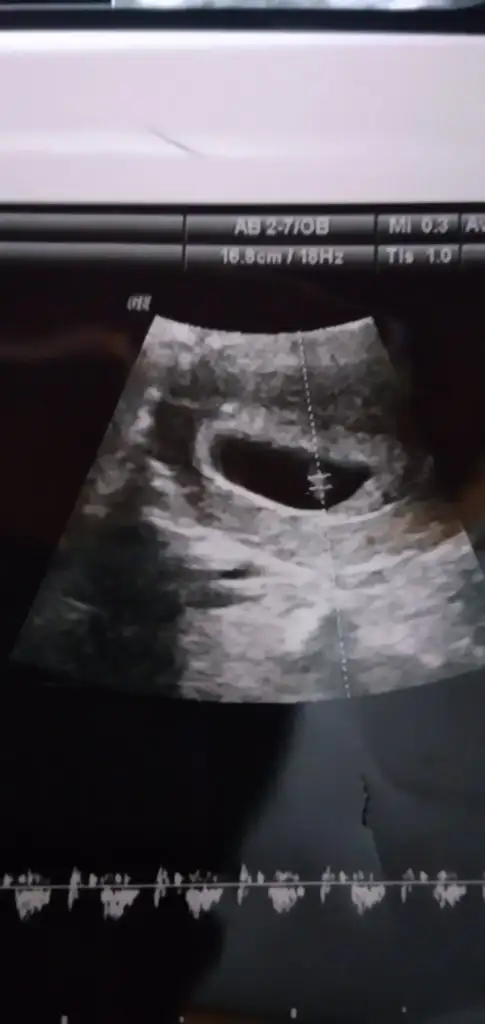

Bana da yorum yapabilir misiniz?

1.Resim 6+3

2.Resim 11+5

3.Resim 13+4